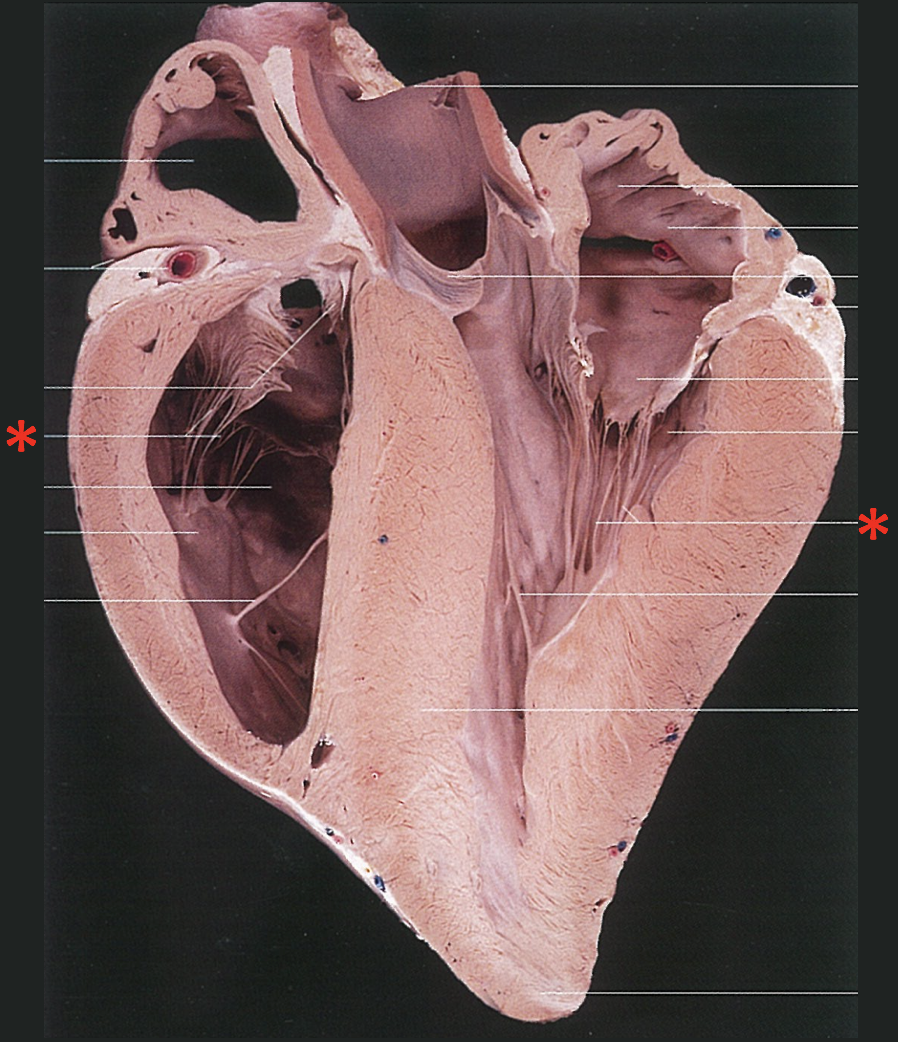

8

Great Papillary Muscle

9

Small Papillary Muscle

10

Subarterial Papillary Muscle

29

**M. papillaris subauricularis** * Located under the auricle

30

**M. papillaris subatrialis**